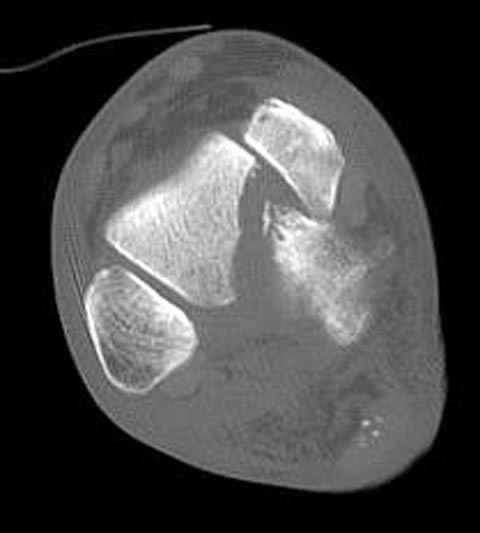

В декабре у меня был пациент с политравмой и аналогичным повреждением тарана с подвывихом в таранно- ладьевидном суставе, единственное отличие - отломок головки тарана был меньше по размеру и фрагментирован, поэтому его фиксация была невозможна.

Для доступа к задне-медиальному суставному фрагменту я выполнил косую остеотомию внутренней лодыжки у её основания -получается хороший доступ к голеностопу, адекватный обзор и возможность восстановить суставную поверхность. фрагмент фиксировал двумя 3,5 мм спонгиозными винтами с неполной резьбой, *утопив* головки винтов в кость. Аналогичная фиксация и двумя тягловыми винтами и внутренней лодыжки. \в качестве альтернативы для

фиксации фрагмента тарана можно было бы использовать и герберт винты, но по организационным причинам :-(( набора не оказалось под рукой).

Повторный осмотр назначил через 2 мес с момента операции. Отдаленных наблюдений такого подхода у меня нет( достаточно редкий тип повреждений таранаHawkins II), но наблюдения в ближайшем послеоперационном периоде выглядели вполне прилично, на мой взгляд.